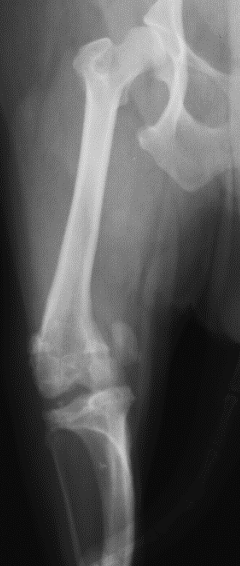

What is shown in this radiograph?

A

lateral bowing of distal femur and medial bowing of proximal tibia consistent with MPL